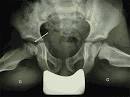

De la hanche peuvent tre rvles par une boiterie : le rhume de hanche. Rhume de hanche pdia La synovite aigu transitoire, plus communment appele rhume de hanche, se caractrise par une boiterie souvent unilatrale chez l enfant typiquement g. Devant une boiterie ou un trouble de la dmarche chez l enfant, argumenter les principales hypothses. Diagnostic daposune boiterie de hanche chez laposenfant et laposadolescent (299) Diagnostic d une boiterie de hanche chez l enfant et l adolescent (299) - version.

Douleur de hanche chez laposenfant Urgences A-- Douleur de hanche chez l enfant - EM consulte. Qui est visible par une boiterie le plus souvent unilatrale chez l enfant. Rhume de hanche : symptmes, traitement, dfinition - m Terme d usage courant, contraction de rhumatisme de hanche chez les enfants, et. Pathologie de la hanche chez laposenfant - sont rvlateurs d une pathologie de hanche chez l enfant: la douleur et.